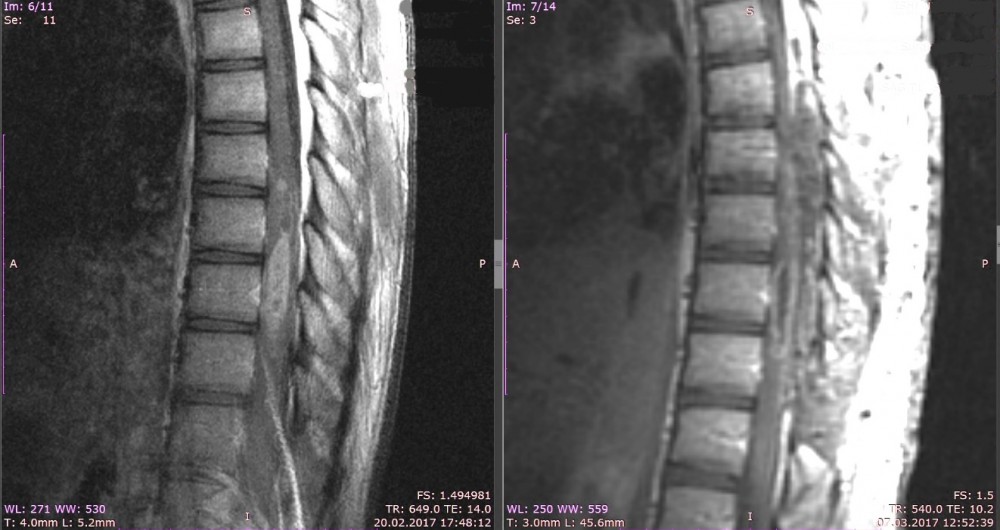

(рус) Злокачественные опухоли спинного мозга